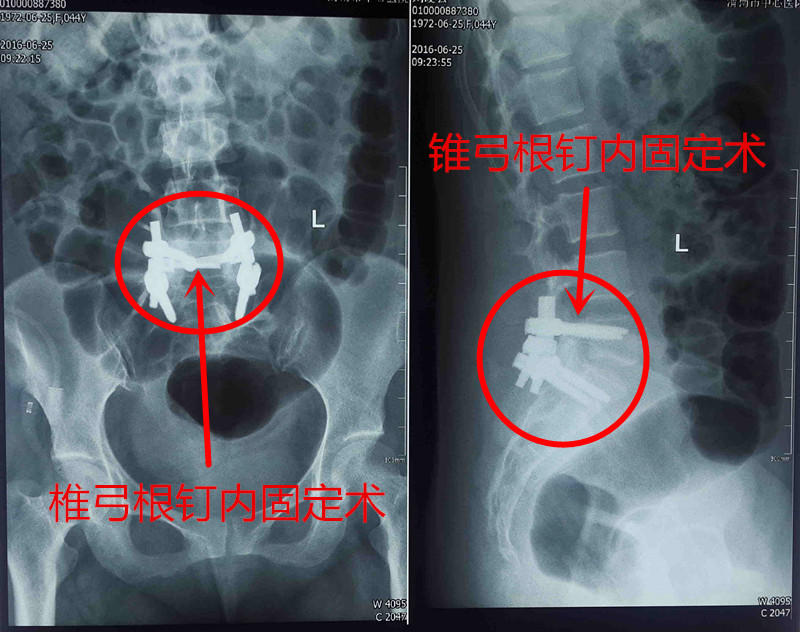

经过充分的术前准备,6月20日,在全身麻醉下,由翁润民主任主刀,在雷广宇、杨杰副主任医师等协助下,行椎管肿瘤切除术、椎体植骨融合内固定术。患者的肿瘤与马尾神经粘连,手术难度较大,稍不注意可能导致患者瘫痪。经过2个多小时的努力,终于成功将肿瘤予以摘除。术后患者生命体征平稳,恢复良好。